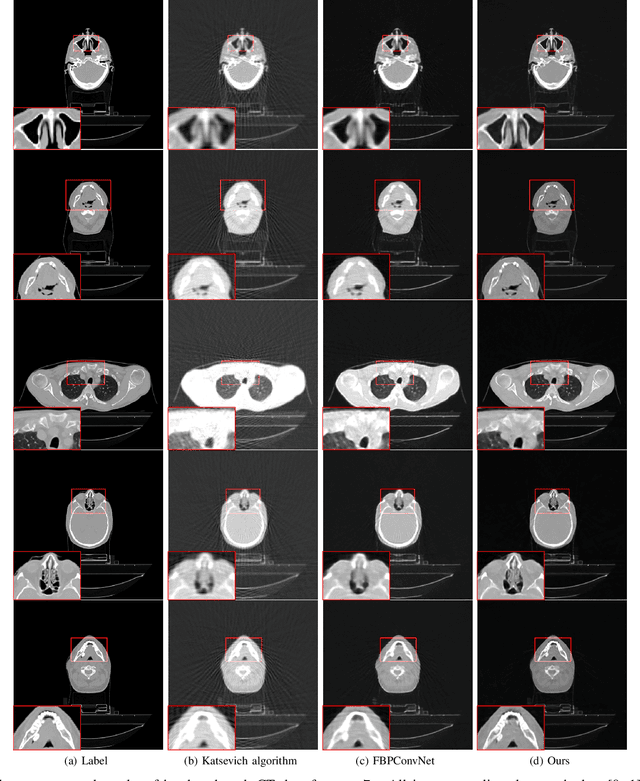

Abstract:In this paper, we propose a new GPU implementation of the Katsevich algorithm for helical CT reconstruction. Our implementation divides the sinograms and reconstructs the CT images pitch by pitch. By utilizing the periodic properties of the parameters of the Katsevich algorithm, our method only needs to calculate these parameters once for all the pitches and so has lower GPU-memory burdens and is very suitable for deep learning. By embedding our implementation into the network, we propose an end-to-end deep network for the high pitch helical CT reconstruction with sparse detectors. Since our network utilizes the features extracted from both sinograms and CT images, it can simultaneously reduce the streak artifacts caused by the sparsity of sinograms and preserve fine details in the CT images. Experiments show that our network outperforms the related methods both in subjective and objective evaluations.